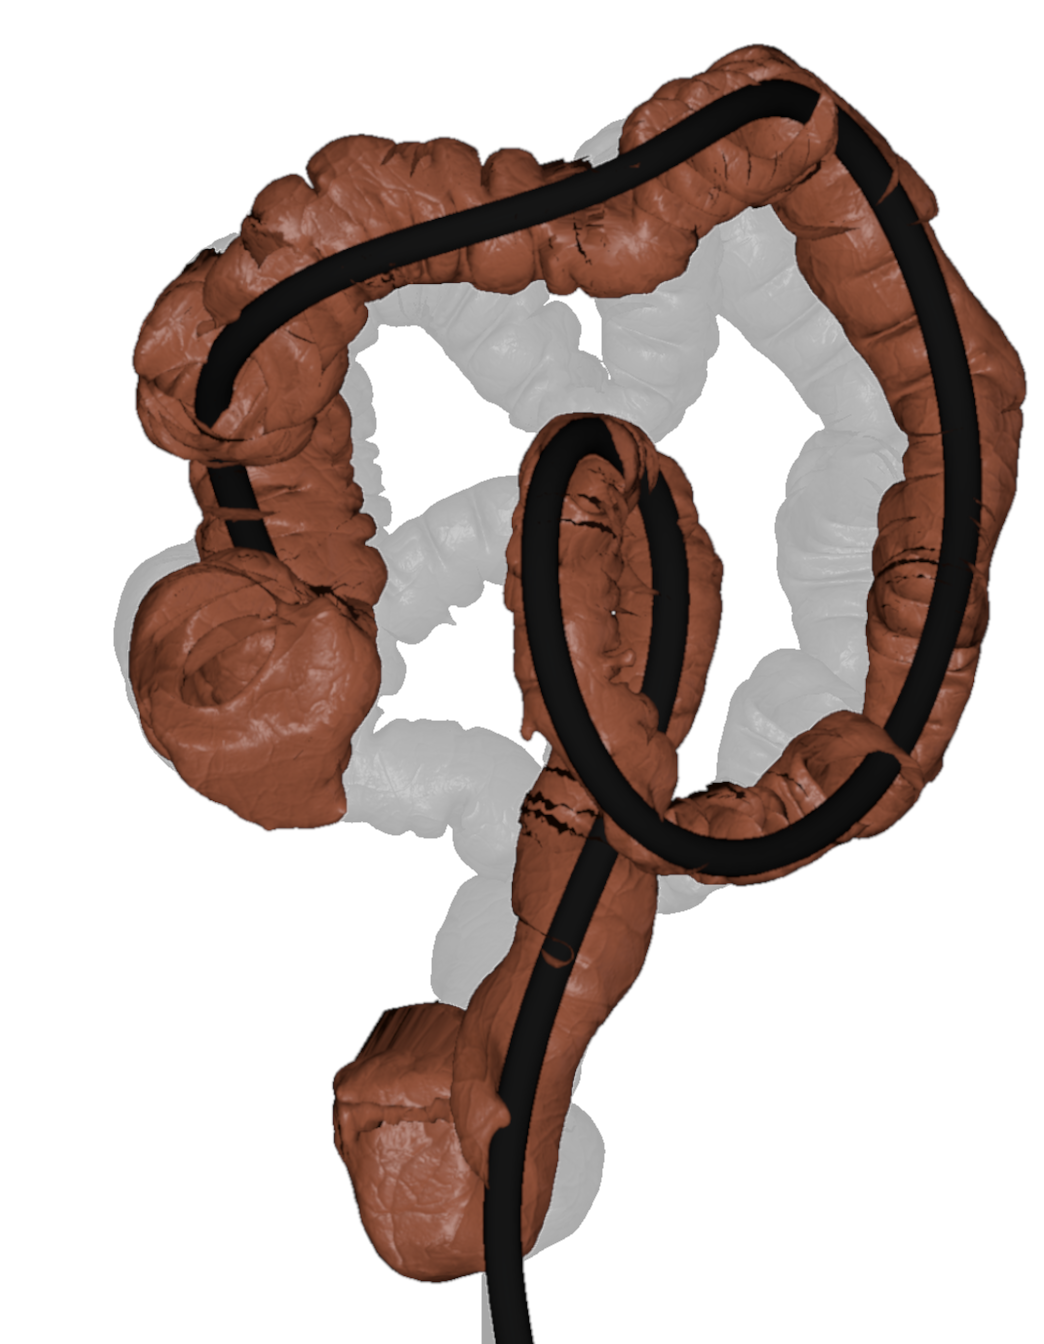

One of our main contributions is a simulation pipeline divided into three main parts, starting with the acquisition and reconstruction of the colon from a real patient CT (a). Then, the colon centerline is extracted and used to build a spline skeleton (b), which will be used to model the colon and the endoscope. The physical deformation is produced using an XPBD formulation and a tailored collision detection method during the simulation (c).